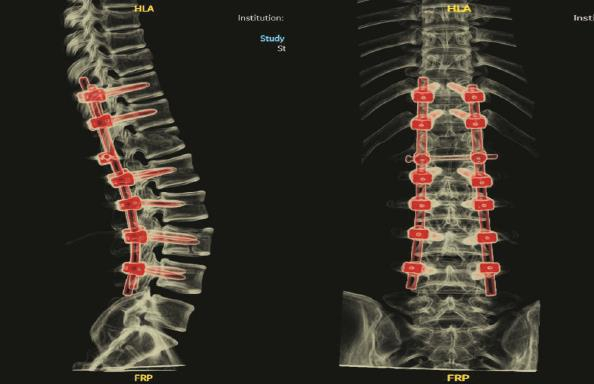

右下图:术后CT示椎体内固定位置稳定,骨折端对位、对线好

儿中心骨科王志刚主任团队接诊后,对孟迪的病情进行了详细的分析,为其制定了个性化的手术方案。由于患者系严重损伤所致的脊柱不稳定骨折伴神经损伤,已出现双下肢截瘫,病情危重,且存在神经压迫、损伤,为重建其脊柱稳定性,为了术后孩子能负重坐起,选择术中同时行减压手术,为神经脊髓功能的部分恢复创造环境,考虑采用目前行业内先进的导航技术及神经功能监测。相较于传统的手术方式,该技术能够在术中实现精确定位,协助医生在患者受伤的椎体精准置钉,从而减少内固定相关并发症,尽可能地避免椎体的疏松和不稳定,降低患儿二次损伤的几率,并大幅缩减手术时间。

最终,凭借着医生丰富的经验和精湛的技术,手术顺利完成。术后第二天,孟迪的双下肢便可自主完成上抬、屈膝等动作,且双足麻木感较此前明显好转,手术成效显著,为后续的康复治疗奠定了坚实基础。目前,孟迪正处于术后康复阶段,医院正继续予以营养神经、抗感染等对症处理,并将根据其恢复情况,及时调整治疗方案。